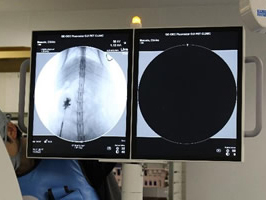

造影で漏れがないか何度も確認

必ず透視下にて漏れがないか何度も確認をします。 透視をしないとシステムや装着部分からの漏れが確認されたり、トラブルが考えられます。

実際、他院で装着して漏れがあるなどの相談をうけることがしばしばあります。

透視下にて実施すれば適切な位置に装着できます。

透視下にて腎盂に入っていることを確認。

ここにカテーテルを装着していきます。

SUBシステムを設置しました。

漏れを確認して終了となりました。